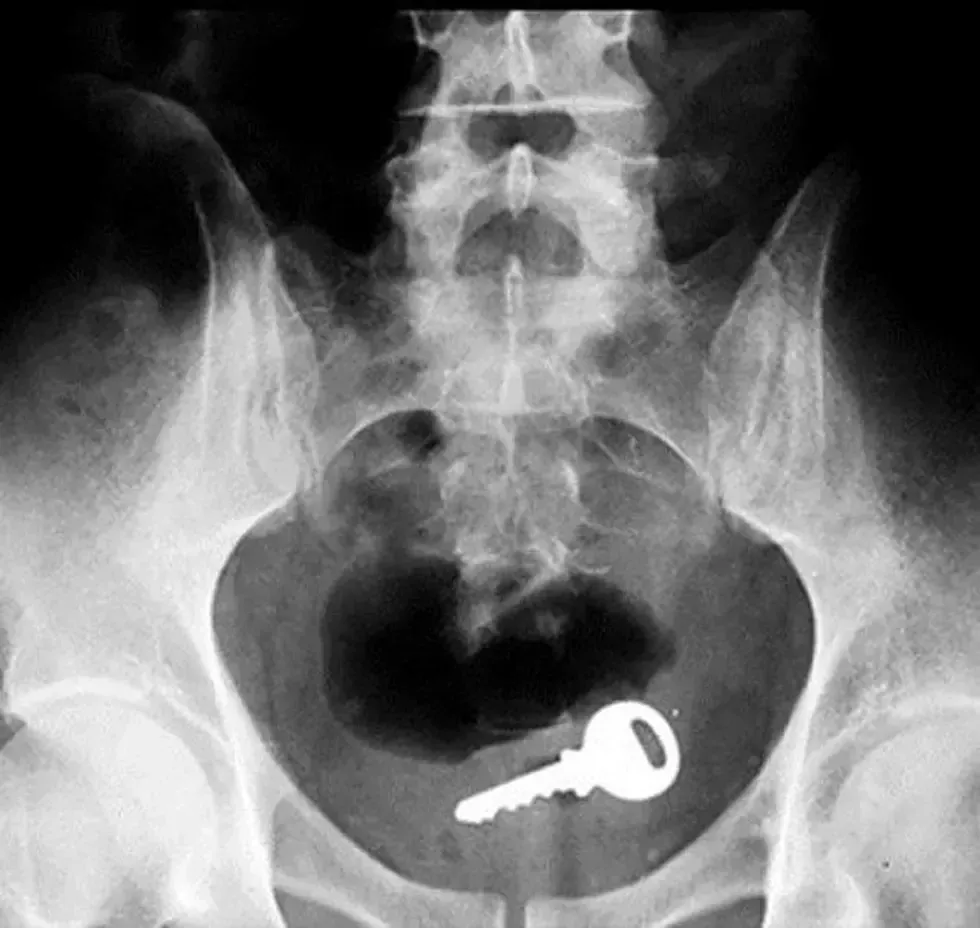

16. A key